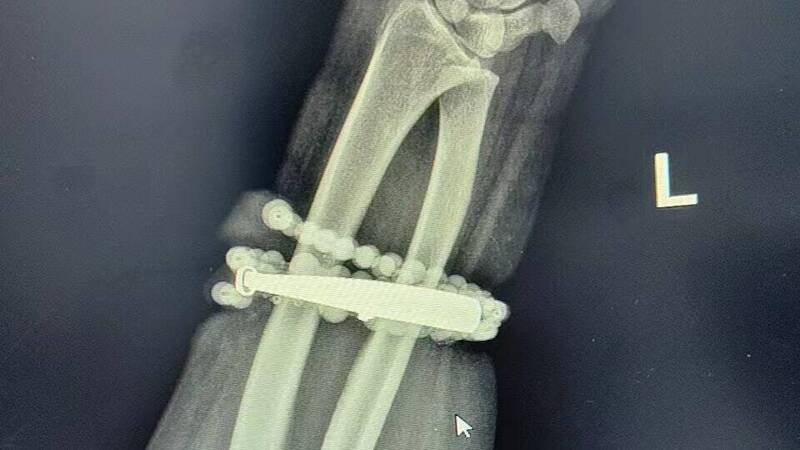

手镯和串珠链「长」进肉里。(图:福建卫生报)

中国福建一名33岁龚姓女子戴银手环和串珠长达10年未摘下,竟长进肉里,差点要截肢。(图翻摄自微博)